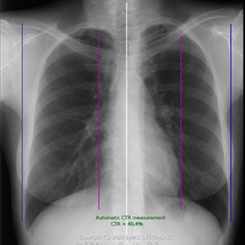

2)CTR計測

これまで手動で計測していたCTR(心胸郭比)をAIで自動計測します。